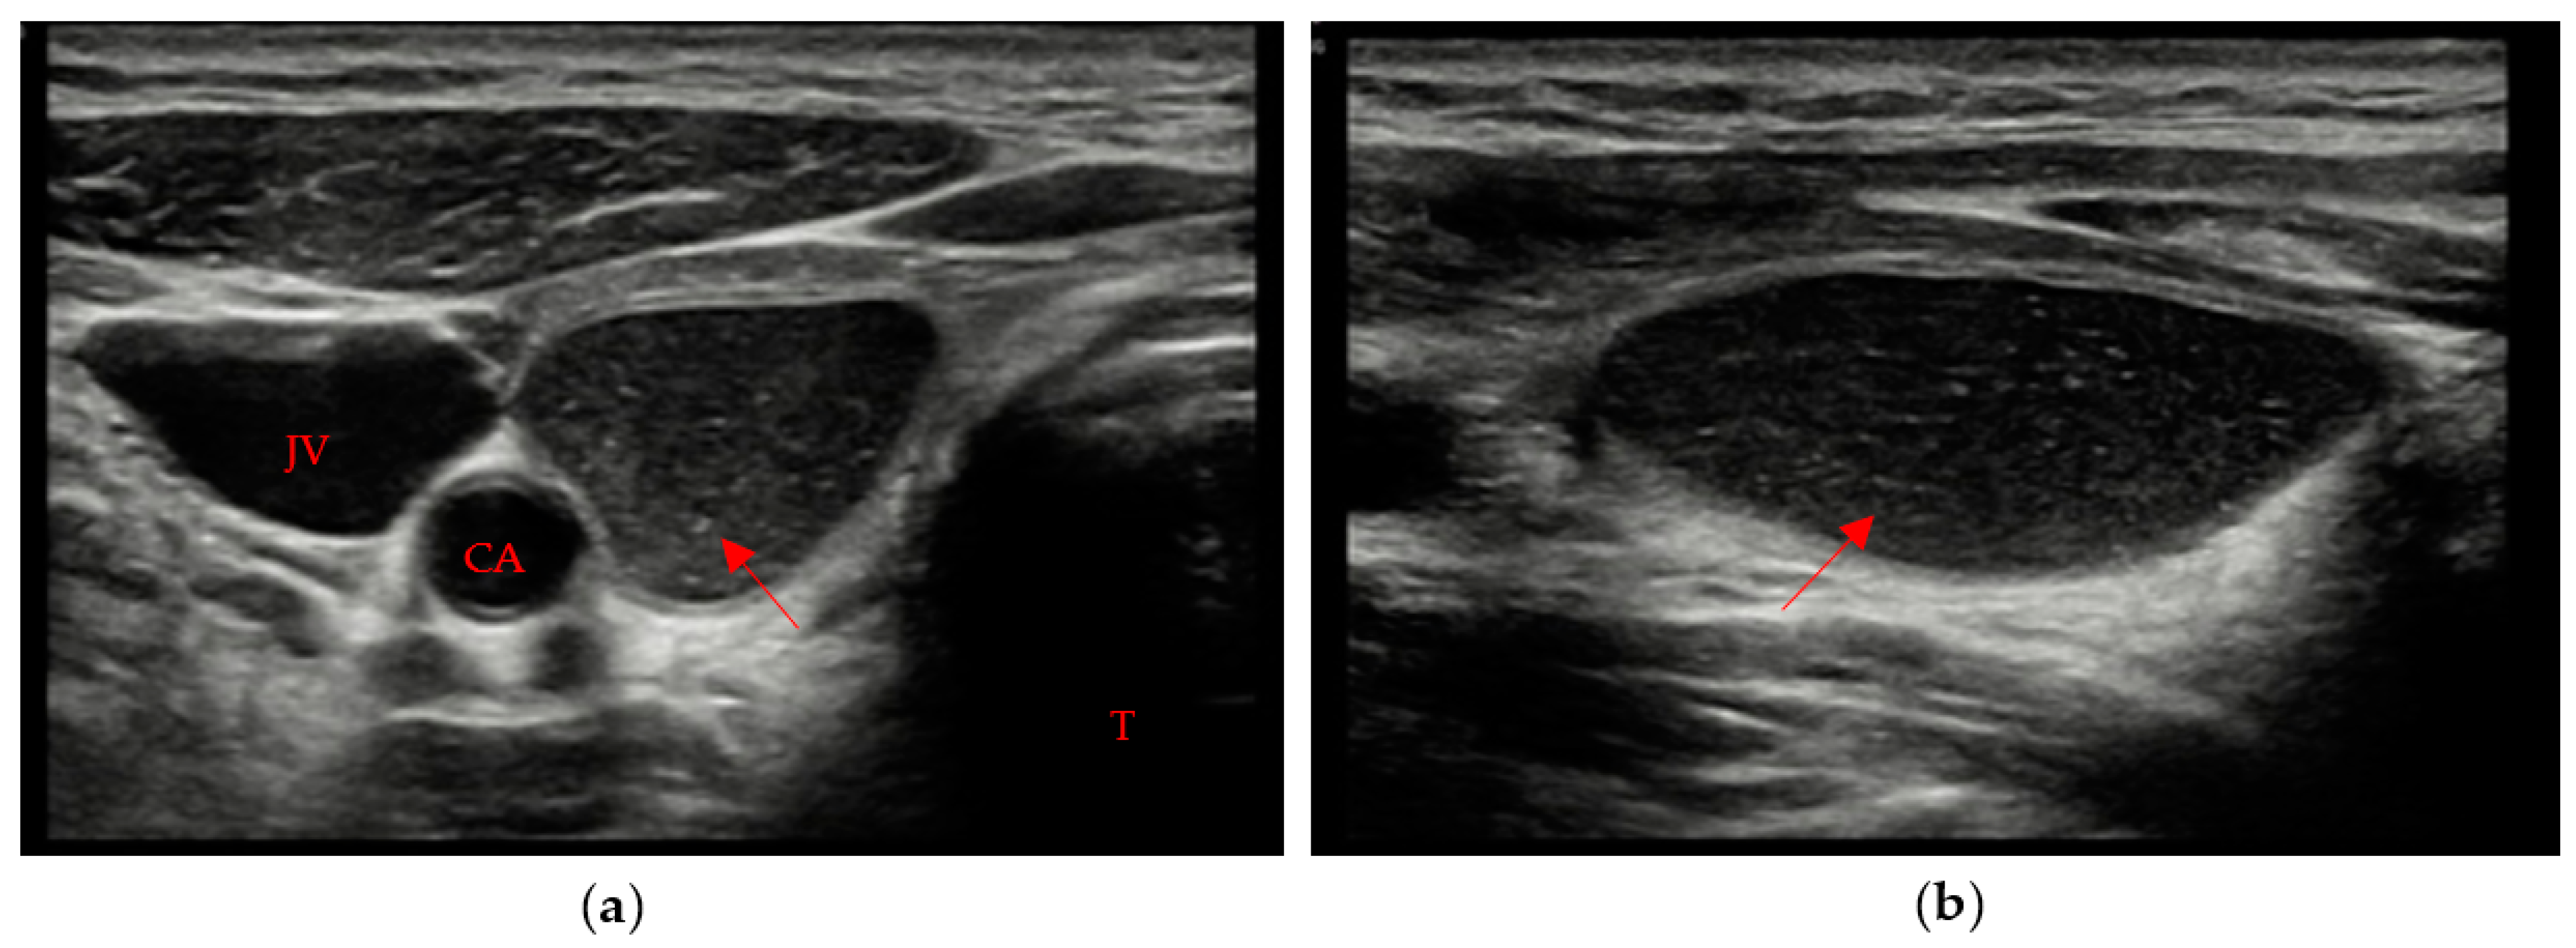

• A markedly hypoechoic pattern with well-defined margins, often with evidence of a peripheral halo (pseudo-capsule appearance), was found in 13 patients, which is approximately 34% of patients with evidence of residual swab (Figure 1a,b).

Figure 1. Residual swab pattern (red arrow) 1, characterized by a markedly hypoechoic pattern with an ecostructure of hyperechoic spots and well-defined margins; (a) Longitudinal view; (b) Axial view. Jugular vein (JV), Carotid artery (CA) and Trachea (T).